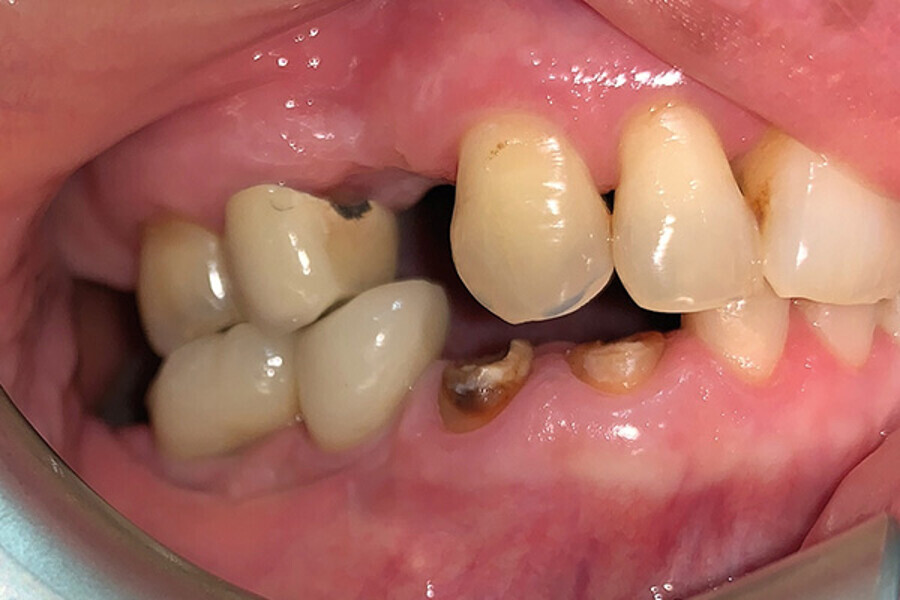

Fig. 1. Vista del caso preoperatorio